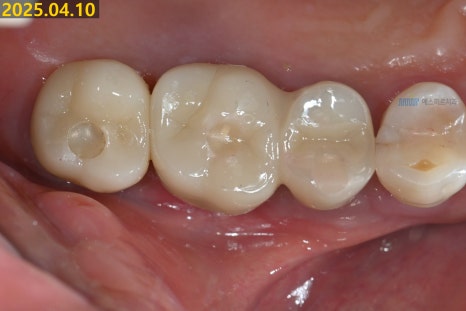

✨ 이번 치료는

염증이 있던 기존 임플란트를 제거하고,

뼈이식과 골유도 재생술을 동반한

임플란트 재식립까지

잘 마무리되었습니다.

(※ 환자 동의하에 제공된 이미지입니다)

환자분은 임플란트 치료를 모두 마무리하셨고

정기 검진을 통해 상태를 꾸준히 점검해드릴 예정입니다 😊